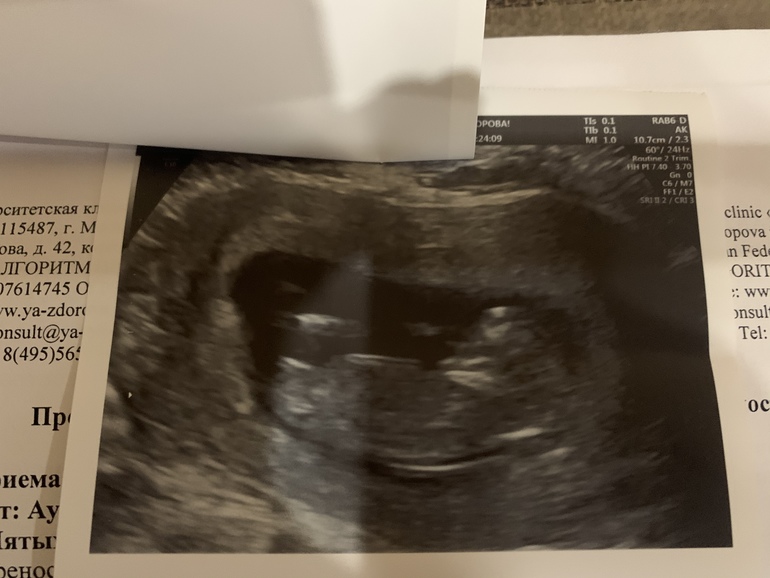

В 12 недель вот такое фото дали